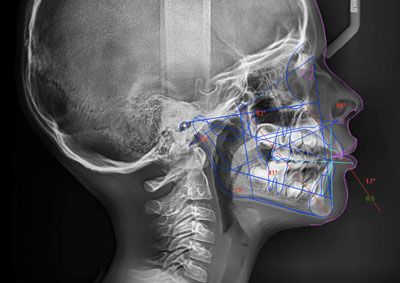

• téléradiographie du crâne de profil

Radio sous plusieurs angles de la mâchoire